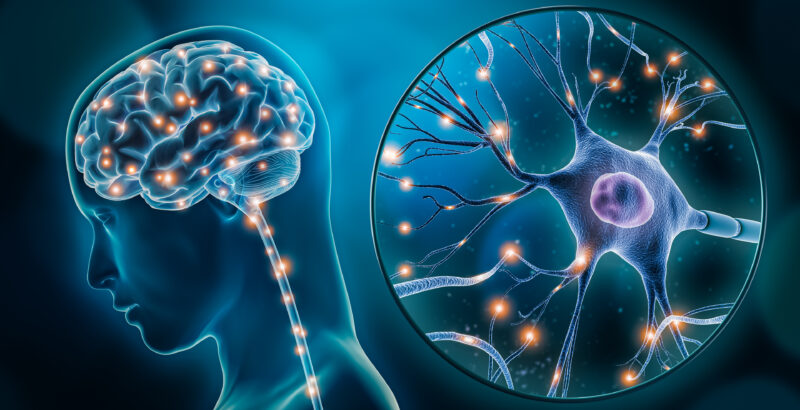

O que é a neuroestimulação? A neuroestimulação é uma técnica médica que utiliza impulsos elétricos de baixa intensidade para modular a atividade do sistema nervoso central e periférico. Ao interferir com os sinais de dor que vão da periferia do nosso corpo para o cérebro, este tratamento oferece um alívio significativo e duradouro para muitas […]